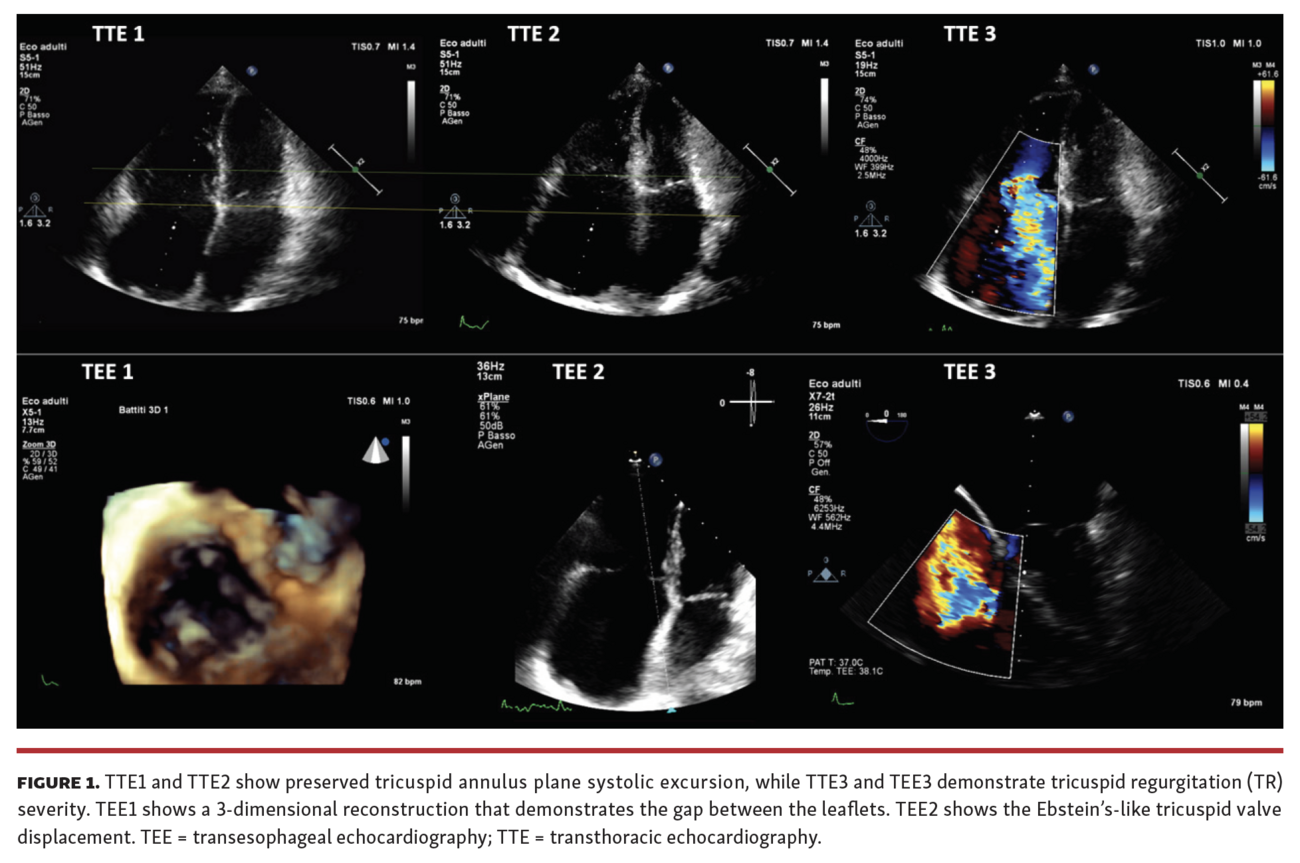

The preprocedural cardiac magnetic resonance (CMR) showed a right ventricular end-diastolic volume index (RVEDi) of 79 mL/m2, right ventricular end-systolic volume index (RVESi) of 27 mL/m2, tricuspid regurgitant volume (TRV) of 56 mL, and tricuspid regurgitant fraction (TRF) of 67% (Figure 3). Due to the patient's history of breast cancer radiotherapy and high surgical risk, the heart team preferred a transcatheter approach as the treatment option. The first TriClip (Abbott Vascular) was successfully implanted in the anteroseptal commissure, determining annulus size reduction and the subsequent necessity of transesophageal echocardiographic projection change to assess the result due to acute reshaping (Figure 4 and Figure 5; Video Series). A second TriClip was implanted in the anteroseptal commissure, highlighting the changes in the valvular plane and cardiac axis (Video Series). Residual TR was trivial (Video Series). The acute remodeling was confirmed at the CMR follow-up (Figure 6), with significant volume and TR reductions (RVEDi, 39 mL/m2; RVESi, 18 mL/m2; TRV, 8 mL; and TRF, 23%).